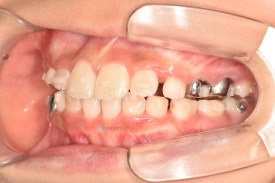

기존 교정장치와 같은 철사 찔림이 없고 확장과 치아배열이 동시에 잘되는 투명교정장치입니다. 착용한 상태에서도 거의 티나지 않아 아이들이 좋아합니다.😁

투명교정 10개월차입니다.

치료 후 - 유치 어금니들이 빠지고 영구치가 맹출하고 있습니다.송곳니가 나올 공간을 충분히 마련하며 확장하여 고른치열을 완성했습니다.